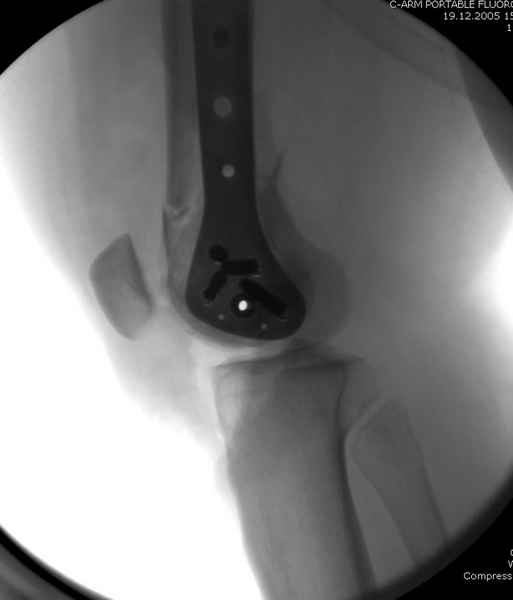

Уважаемые коллеги! От имени Алексея Смирнова всем спасибо за обсуждение. Больной прооперирован. Снимки в приложении.

Мы бы не стали открывать, такие переломы срастаются, хотя бы и с краевым дефектом. То есть если удалять стержень потом, то сильно попозже обычного. В приложении пример. Сразу после операции и через 11 мес. Понятное дело, пациент к тому времени давно и не хромал, и функция колена была полная.